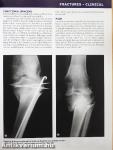

Orthopaedic Physiotherapy

Megjegyzés: Fekete-fehér fotókkal, egy színnel színezett ábrákkal.

Orthopaedic Physiotherapy Orthopaedic Physiotherapy Orthopaedic Physiotherapy Orthopaedic Physiotherapy Orthopaedic Physiotherapy